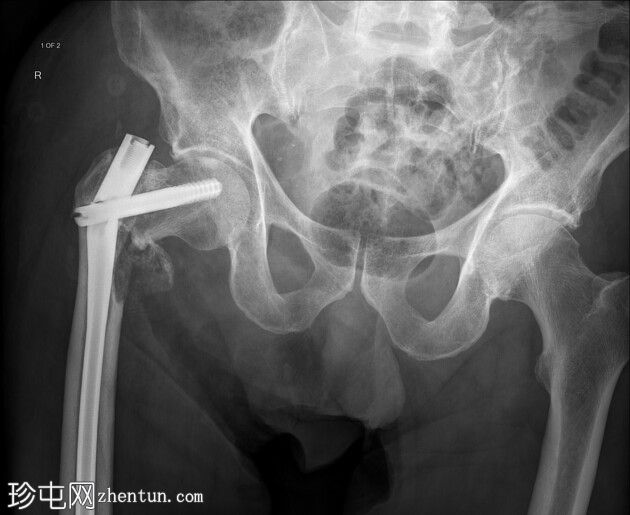

右侧髓内钉近端骨折(位于拉力螺钉孔位)。

空心髋螺钉组件完好。

股骨转子间骨折延伸至股骨近端转移灶,小转子粉碎。

在本例中,髓内钉断裂发生在拉力螺钉孔(穿过股骨颈的螺钉)的水平,该水平可能是髓内钉本身较薄弱的部位。靠近该水平的溶骨性病变可能导致了不稳定性和髓内钉的异常应力。